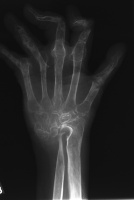

Xrays show radiocarpal collapse, proximal migration of the proximal phalanges, flail PIP joints and loss of the proximal half of the dorsal cortex of the proximal phalanges.

Her greatest desire was pinch reconstruction. This was approached in two stages: wrist fusion, implant removal and fusion of the index and middle PIP joints, followed by index and middle MCP arthroplasties. There are several alternative approaches, including index MCP fusion and revision PIP arthroplasties.

Below are xrays after the first set of reconstructions.